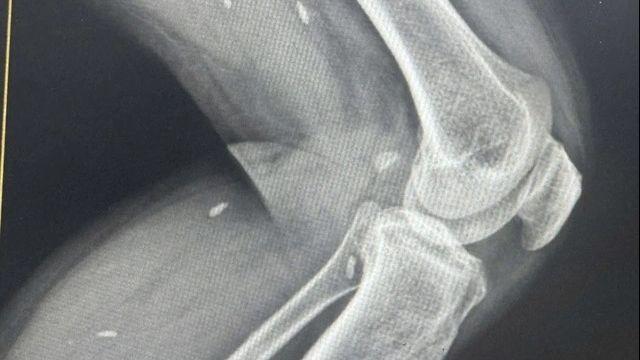

Ngày 27/7/2021, Bệnh viện Hữu nghị Việt Đức tiếp nhận trường hợp em N.N.H (18 tuổi, Thanh Miện, Hải Dương) đến viện trong tình trạng đa chấn thương, cần được mổ sớm để duy trì sự sống. Tuy nhiên, em H thiếu máu để mổ. Kho máu của bệnh viện cạn kiệt, người nhà em đã hiến máu trước đó nên không thể tiếp tục hiến máu cho em.

Trong tình thế nguy cấp đó, 3 nhân viên của khoa Khám bệnh là anh Trần Văn Chanh, Nguyễn Mạnh Hiền, Hồ Văn Quyền đã không một chút đắn đo đứng ra hiến máu giúp em H có máu để phẫu thuật. Tất cả được diễn ra khẩn trương tại Trung tâm Truyền máu của bệnh viện. Nhờ được truyền máu kịp thời, em H đã được các chuyên gia của Bệnh viện Hữu nghị Việt Đức tiến hành phẫu thuật và trải qua cơn nguy kịch, sức khỏe đang dần bình phục.

Là bệnh viện ngoại khoa hạng đặc biệt tuyến đầu của cả nước, mỗi năm mổ trên 70000 ca chủ yếu là đa chấn thương, chấn thương phức tạp nên bệnh viện Hữu nghị Việt Đức rất cần máu để điều trị cho người bệnh. Song ảnh hưởng của dịch Covid-19 khiến nguồn máu dự trữ phục vụ cho công tác cấp cứu và điều trị tại các cơ sở y tế nói chung hiện đang bị thiếu hụt trầm trọng.